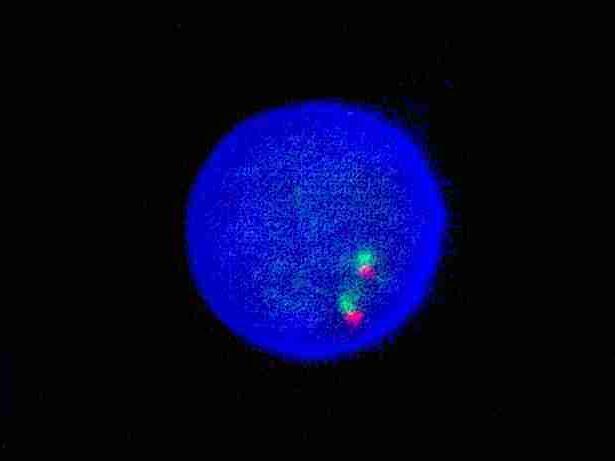

FGFR1 dual color probe

FGFR1 gene 3’ end labeled as orange, with a length of 504 kb; FGFR1 gene 5’ end labeled as green, with a length of 626 kb.